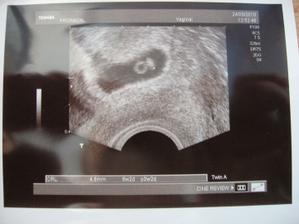

První fotečka kulíška